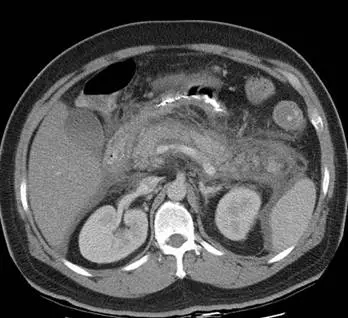

病人主訴急性上腹疼痛,噁心嘔吐,腹部電腦斷層檢查呈現如圖,下列那一項診斷最正確?

本題考察急性上腹痛合併噁心嘔吐的鑑別診斷,重點在於判讀腹部電腦斷層(CT)影像所呈現的胰臟炎(acute pancreatitis)特徵性變化,並與急性胃炎(acute gastritis)、缺血性腸道疾病(ischemic bowel disease)及急性十二指腸炎(acute duodenitis)加以區分。

腹部 CT 橫切面(axial view)顯示:

胰臟(pancreas):胰臟體積明顯腫大,密度不均,邊界模糊不清。胰臟周圍(peripancreatic)脂肪組織出現典型的脂肪絞扭影(fat stranding),表現為脂肪密度升高、網狀混濁,反映急性發炎滲出。

胰周積液(peripancreatic fluid):胰臟周圍可見液體積聚,影像顯示胰腺前方及周圍有低密度液體,符合急性胰臟炎之胰周積液(peripancreatic fluid collection)。

周圍結構:雙側腎臟顯影對稱,無明顯腎臟病變。腸道無明顯腸壁增厚或灌注缺損跡象。胃壁無顯著增厚。

Balthazar 分級(CT Severity Index, CTSI):依據本影像所見,至少符合 Grade C(胰臟腫大 + 胰周脂肪炎症)以上,顯示中等至中重度急性胰臟炎。